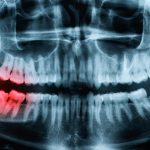

虫歯治療

根管治療